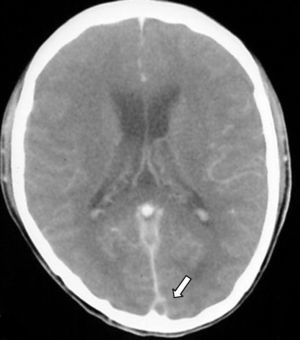

Signo del triángulo denso. Se puede observar en las primeras dos semanas hasta en el 60% de los pacientes y corresponde a un trombo fresco en la parte posterior del SSS (fig. 2). No es específico y existen falsos positivos en pacientes con hematocrito elevado o deshidratación.